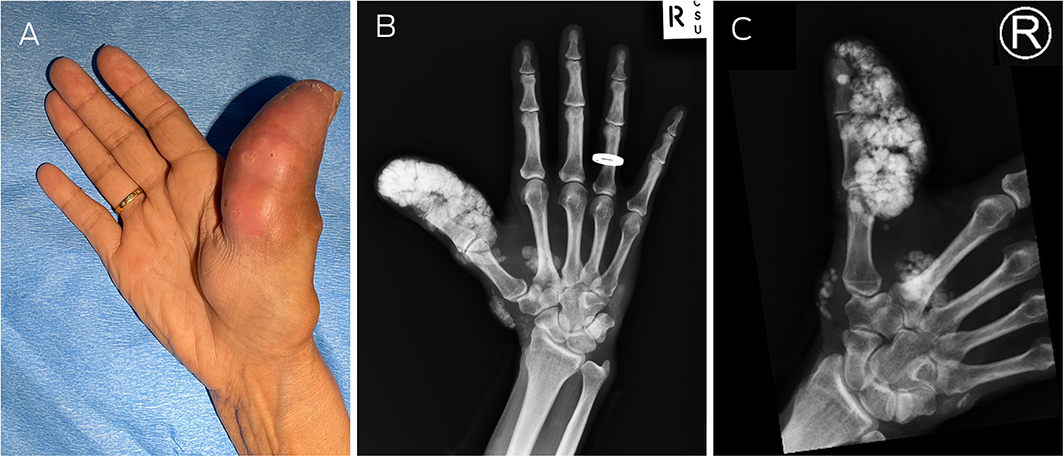

The patient gave written consent for publication.